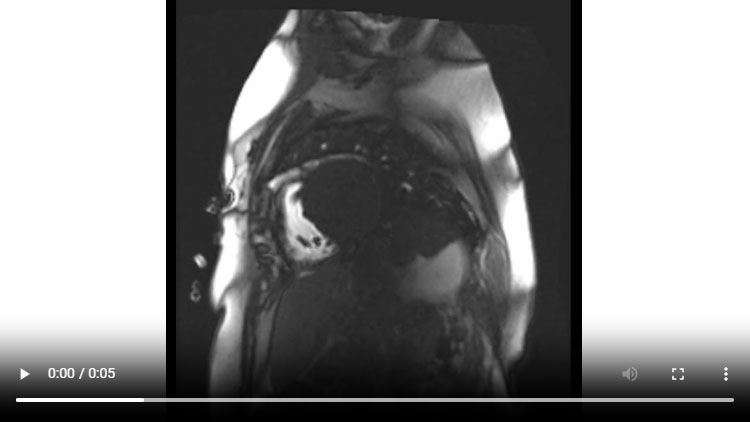

Figure 3A : Séquence de perfusion premier-passage au repos - Coupes petit-axe basal

Figure 3B : Séquence de perfusion premier-passage au repos - Coupes petit-axe médian

Figure 3C : Séquence de perfusion premier-passage au repos - Coupes petit-axe apical

Figure 3D : Séquence de perfusion premier-passage au repos - Coupes 2-cavités

Figure 3E : Séquence de perfusion premier-passage au repos - Coupes 4-cavités

Figure 7 : Séquence de perfusion premier-passage au repos

Présence d’une hypoperfusion sous-endocardique diffuse (flèches jaunes) correspondant à des troubles de la microcirculation décrits sur les modèles animaux d’amyloses cardiaques.